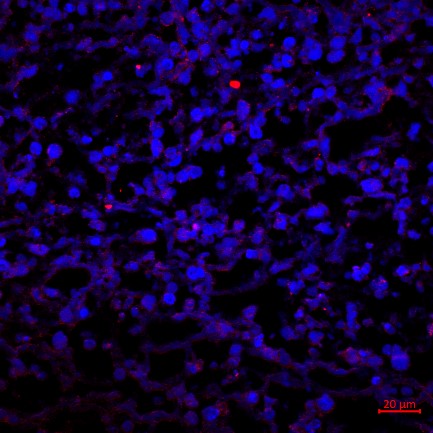

13、免疫荧光实验结果(小鼠肿瘤CBS抗体举例)

免疫荧光实验结果解读:选择激光共聚焦显微镜观察细胞核经DAPI染色后呈现蓝色,目的蛋白被AF594荧光染料标记而呈现红色。